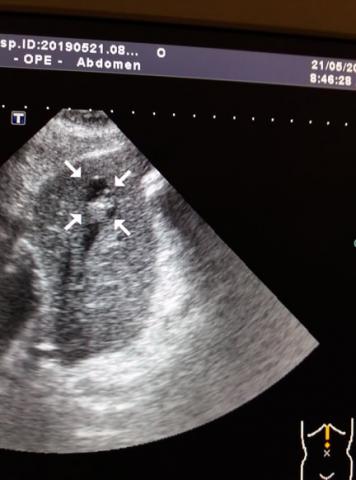

Ми ПЕРШІ в Черкаській області, хто запровадив та здійснює найсучасніший вид ультразвукового дослідження – фіброеластометрію зсувної хвилі та компресійну еластографію (мультипараметрична діагностика). Фіброеластометрія зсувної хвилі дозволяє швидко та якісно встановити ступінь фіброзу печінки за шкалою metavir (кількісний аналіз), а компресійна еластографія дає можливість з високою точністю діагностувати ступінь злоякісності новоутворень (якісний аналіз).

Фіброеластометрія зсувної хвилі та компресійна еластографія

Ми перші в Черкаській області, хто з середини 2018 року здійснює найсучасніший вид ультразвукового дослідження – фіброеластометрію зсувної хвилі та компресійну еластографію.